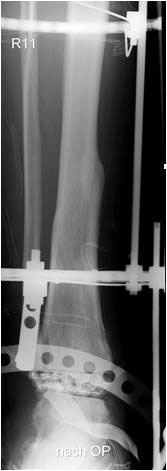

• Revision einer gescheiterten Fusion des OSG/ USG (Abbildung 3, Abbildung 4).

• Pseudarthrosen (Abbildung 5, Abbildung 6).